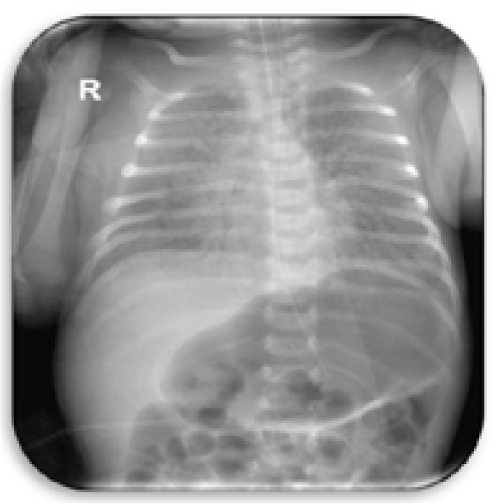

Case Report

A Case Report on Familial Hypokalemic Periodic Paralysis

Irina Batista Rosa. 12(1): 83-87.